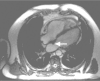

Fig. 1 On 4 November 2009, cardiovascular magnetic resonance showed a small (10 × 10-mm) mass (arrow) attached to the left atrial septum.